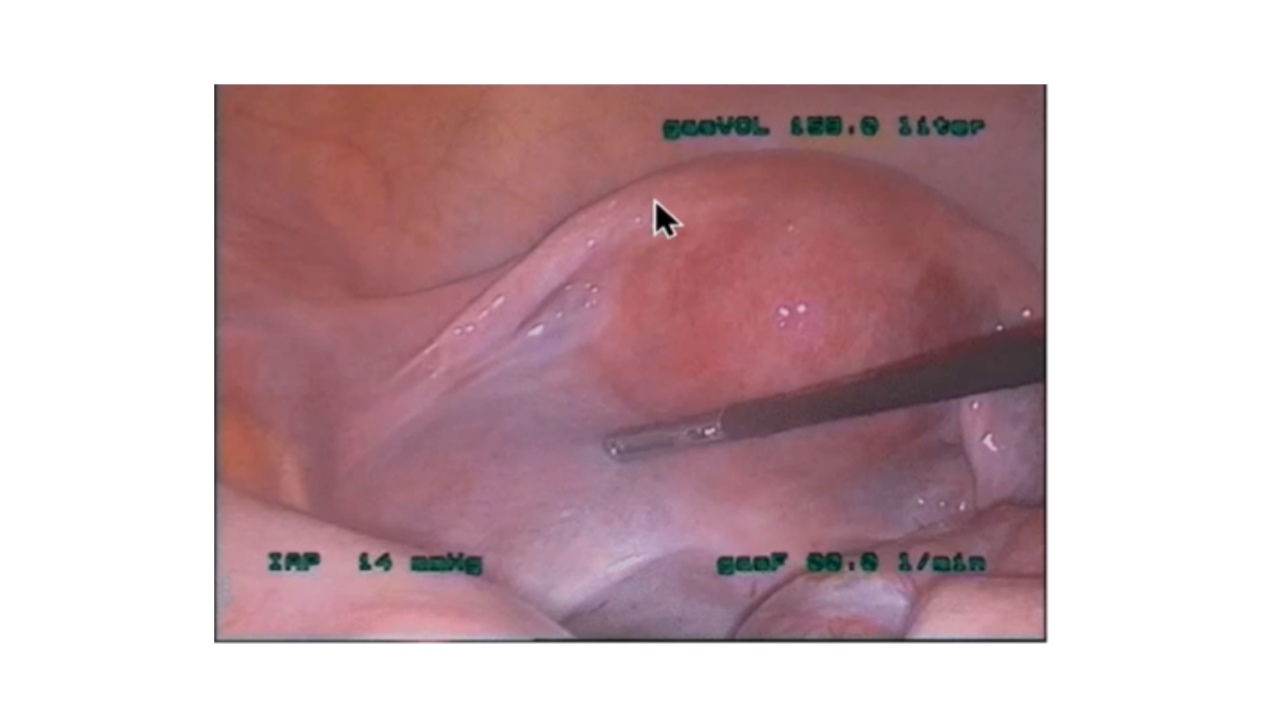

腹腔镜检查左侧输卵管可见不到1cm的残端,其次是缺失的中管段(峡部约2cm),然后是正常的远端,两部分由输卵管系膜连接。右侧有输卵管中缩窄。双侧卵巢正常。